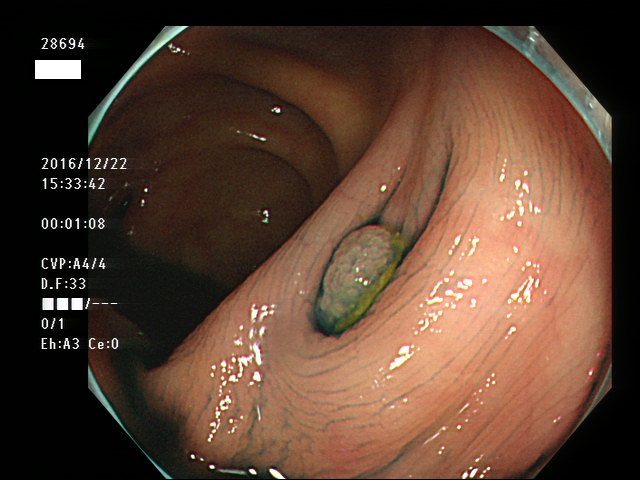

回盲弁(小腸と盲腸の境界)や、憩室の中、炎症で腫れた部位などは複雑に凸凹しており、ここに微小な病変、平坦な病変があると認識が困難になり見落としの危険が高くなります

| 憩室内に発生した腺腫 | 憩室内に発生した腺腫 |